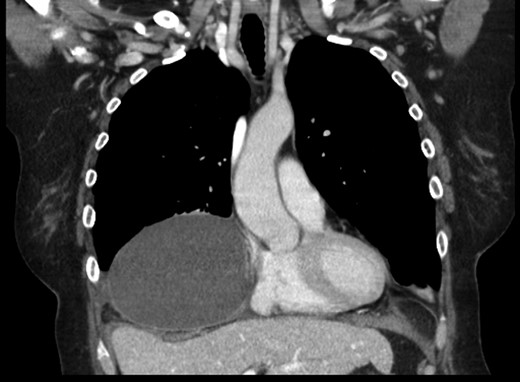

A 69-year-old female was referred to our clinic for an incidental finding of a large Morgagni hernia found on a recent CT chest scan for lung cancer screening. Patient reported occasional shortness of breath after prolonged ambulation but denied chest pain. She did have remote history of acid reflux symptoms but nothing recently. She denied issues with prematurity or issues with development as an infant, chest trauma, or MVA history. She did complain of occasional right shoulder pain but attributed this to arthritis. Denied history of heart attack, stroke, DVT, or PE. She had a 30-pack-year smoking history but quit a year prior. She was up-to-date on her colonoscopy, current within the past year. She denied hematochezia and melena, bowel habit changes or major body weight changes as well as any current abdominal pain. On examination her vitals were within normal parameters. Heart and lungs were unremarkable. Abdominal examination was soft with normal bowel sounds and nontender. Remainder of examination was unremarkable. Laboratory values included a normal CBC and BMP. A CT chest scan had demonstrated a large retroxyphoid hernia of Morgagni involving several loops of small bowel and transverse colon located in the right inferior hemithorax (Figs 1 and 2). No evidence of acute incarceration or strangulation were noted. A detailed discussion was undertaken with the patient regarding her hernia and she was consented for a laparoscopic repair with mesh.

Another slice of the CT scan of the chest revealing the large size of this Morgagni hernia with multiple loops of small bowel and colon in the right inferior hemithorax.